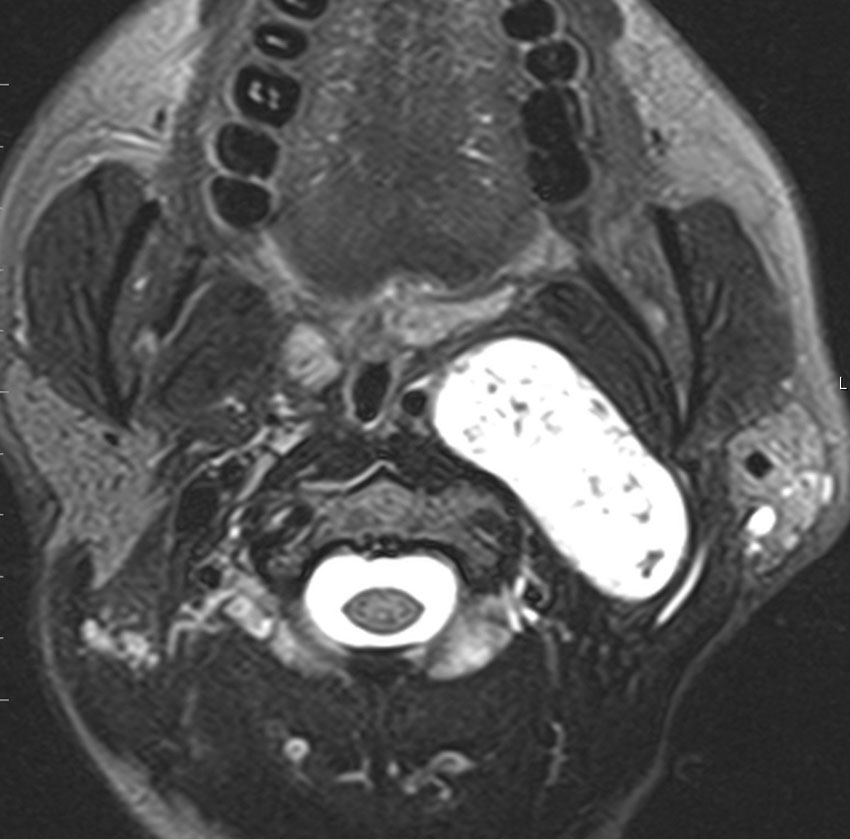

症例:気道狭窄を呈したもの:副咽頭間隙腫瘍 parapharyngeal tumor

頸静脈孔にも腫瘍があり頸部へ伸展した迷走神経鞘腫です。咳が出る,右下にして寝ると痰が詰まる,咽せるという症状で発症しました。摘出すると嚥下障害が出る可能性があるので,9年間経過観察しました。徐々に増大して,正中方向へ伸展して気道狭窄を生じました。睡眠時無呼吸,痰が詰まって苦しくなって夜中に目覚めてしまうという症状になりました。

内部から核出 enucleationしました。腫瘍周辺に迷走神経組織があるので,中心から内部の腫瘍だけを摘出減荷する方法です。左術前,右術後。